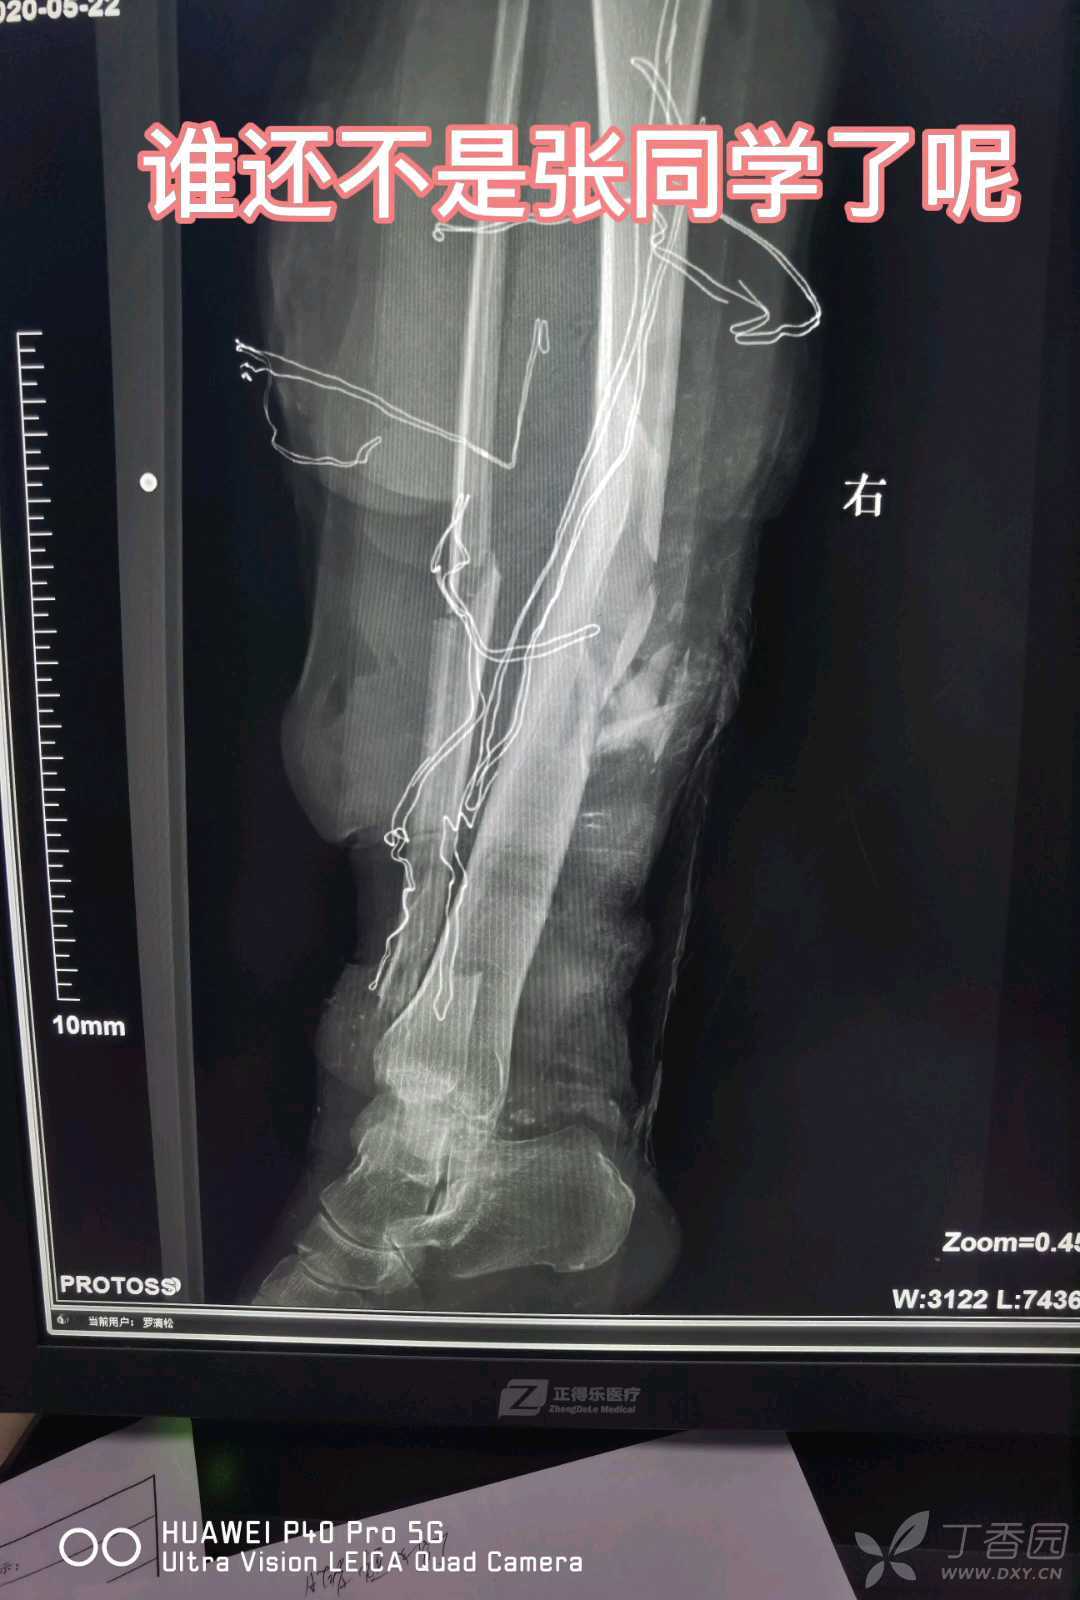

病例“张同学”:论没有趁手工具如何卸掉螺钉。

本视频主要是说卸螺钉技巧

略血腥